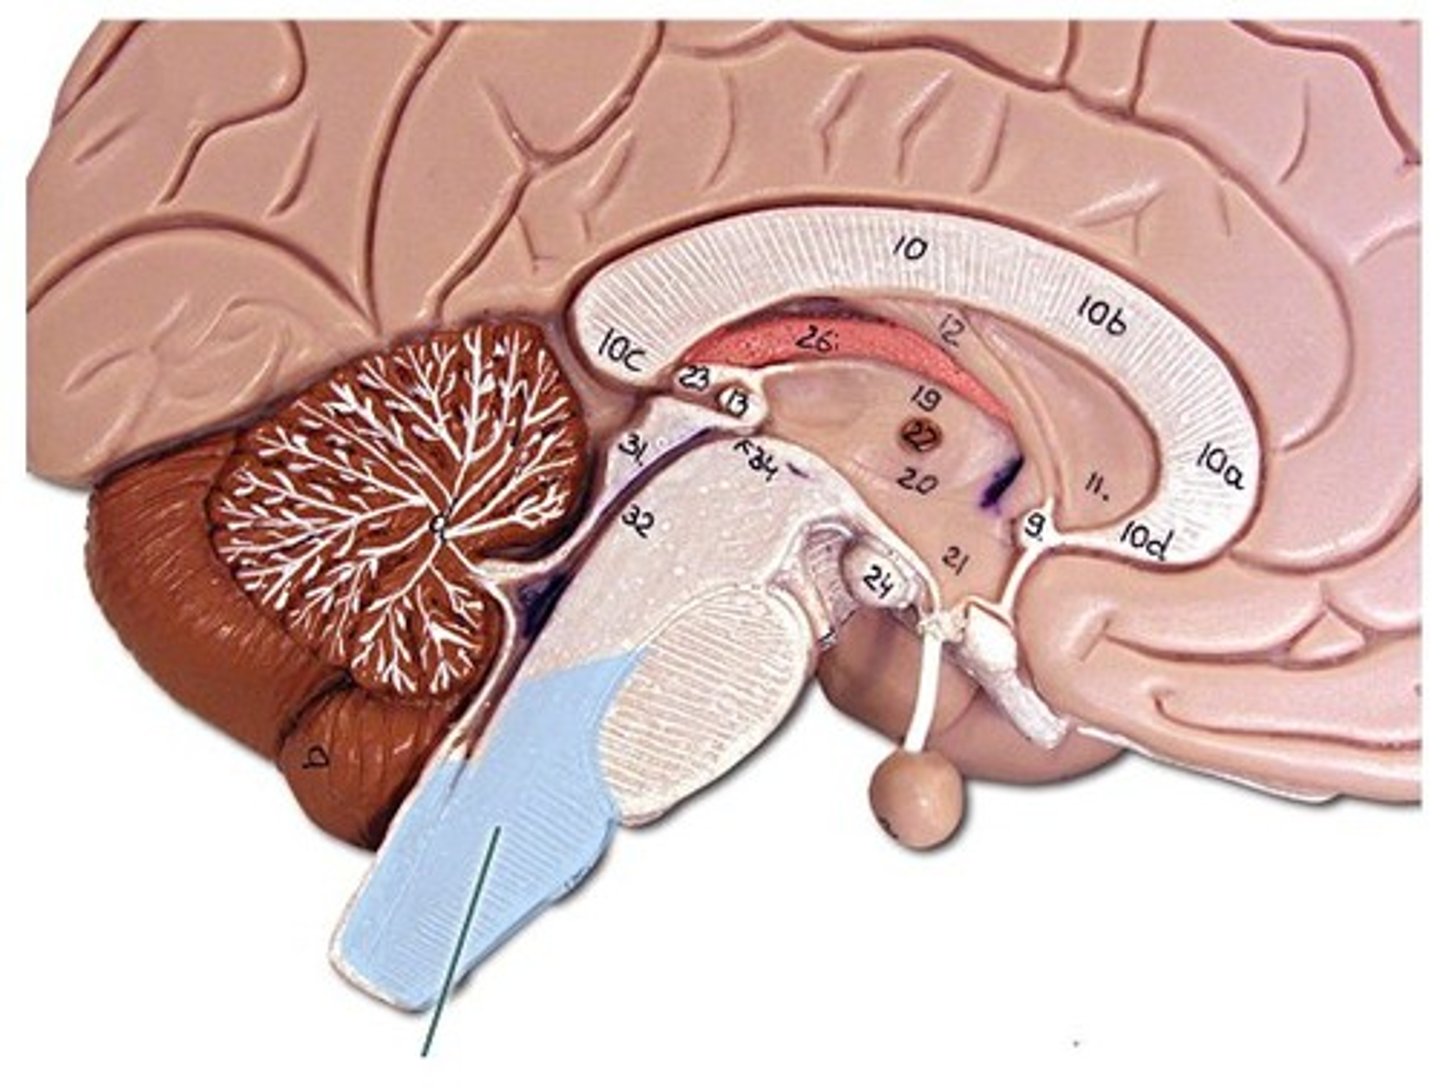

Medulla Oblongata

Structure. Very bottom of brain stem

Olives

Structure

Pyramids

Structure. Front legs of the seahorse

Inferior cerebellar peduncles

Structure. Back of the seahorse legs

Pons

Middle cerebellar peduncles

Structure. Smooth area

Superior cerebellar peduncles

structure. horseshoe shape

Fourth ventricle

Space. Triangle space next to pons/ cerebellum

Rhomboid fossa

Depression. Against pons /bottom of the triangle

Cerebellar part of the 4th ventricle

Structure. Sides of triangle against cerebellum

Thalamus

Structure. Eye on the seahorse

Interthalamic adhesion

feature. Pupil on eye, middle of the eye

Epithalamus

Pineal gland

Hypothalamus

Structure. Nose of seahorse

Infundibulum of the brain

Structure. Cherry STEM right before red part (cherry)

Mammillary bodies of the brain

Structure. Little bump near/ under nose

Optic chiasm

Structure. Shown on the brain/ X-shape

Third ventricle

Space

Corpus callosum

structure, first sombrero

Cingulate gyrus

ridge, bigger sombrero

Fornix

Septum Pellucidum

Choroid plexus

Structure. All pink on model

Lateral ventricles

Space. Ram horns on sides

Interventricular foramina

Passageway. Connects top of ram horns to the center

Cerebral aqueduct

Passageway. Looking at posterior side